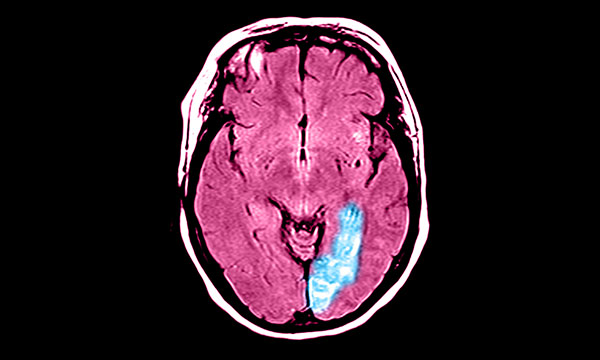

Three studies investigate the association between stroke and depression following the Stroke Association findings this year.